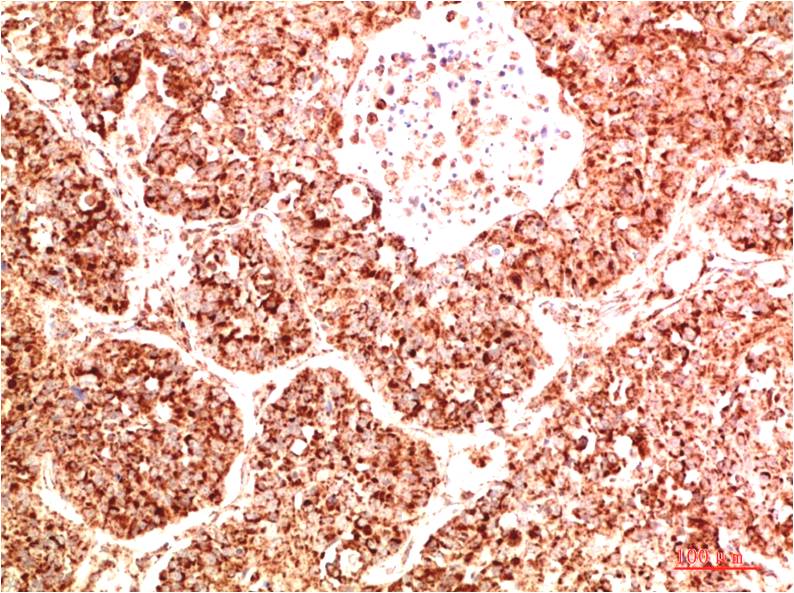

STAT1 Rabbit Polyclonal Antibody

Catalog NO.:BE3403

Applications :WB, IHC

Reactivity :H,R,M

STAT1 is a member of the Signal Transducers and Activators of Transcription family of transcription factors. STAT1 is involved in upregulating genes due to a signal by either type I, type II, or type III interferons

| Recommended dilutions: | WB:1:1,000-2,000 IHC:1:200-500 |

| Specificity: | Antibody can detects endogenous STAT1 protein. |